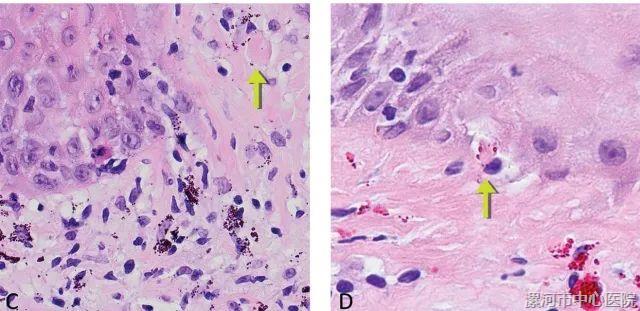

图4. (左)真皮表皮交界处皮炎高倍观,并可见黑色纹身颗粒,淋巴细胞直接侵及胶样小体(Civatte body,箭头所示。即表皮棘层、基底层或黏膜固有层内细胞凋亡形成的圆形或卵圆形小体,平均直径10微米左右,均质嗜酸性,PAS阳性;译者注)。(右)表皮细胞凋亡的例子,凋亡细胞周边可见红色纹身颜料颗粒并有淋巴细胞。